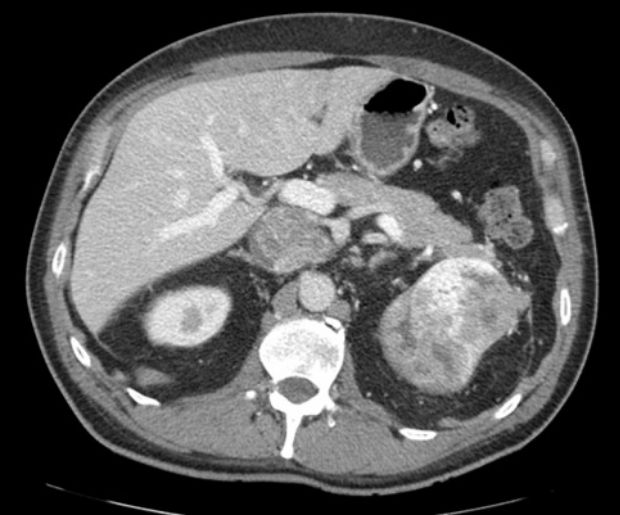

Muž 58 let – světlobuněčný karcinom

Na vyšetření přišel 58letý Jan Vokřálek, který byl předtím vyšetřen praktickým lékařem (PL). Pacient již 3 dny trpí trvajícím otokem pravé dolní končetiny, praktický lékař mu zjistil suspektní tromboflebitidu. Dále trpí dyspeptickým syndromem. Lumbalgií netrpí, hematurii neguje.